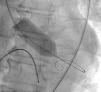

The RCA lesion was crossed with a RotaWire Floppy Guide Wire (Boston Scientific, Natick, MA), which was advanced to the distal RCA. Rotational atherectomy was performed with several passes of a 1.5 mm burr. During rotational atherectomy we aimed to maintain the patient's heart rate 15–20 bpm above resting heart rate to prevent any potential bradycardia and subsequent hypotension. A 3.0 mm×12 mm Resolute drug-eluting stent (DES) (Medtronic, Minneapolis, USA) was deployed in the ostium of the RCA at 18 atm and post-dilated with a 3.5 mm×12 mm non-compliant balloon, with an excellent angiographic result (Figure 2).